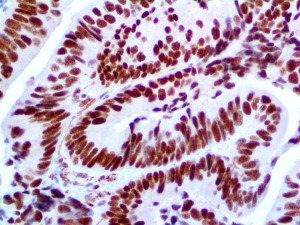

The first cytokines released are interleukin 1β (IL-1β) and tumor necrosis factor-α (TNF-α), which attract a variety of circulating white blood cells (WBCs) to the infection site, including neutrophils, monocytes, macrophages, and natural killer (NK) cells. This response, along with the antipathogenic chemicals released by these cells (i.e., complement), comprise the innate immune response. These cells directly attack the invading pathogen and also release additional cytokines, chief among them interleukin-1 and 6 (IL-6). IL-6 is essential for invoking the adaptive immune response, which calls T-cells, B-cells, and T helper (Th) cells to the infection site. IL-6 also stimulates further recruitment, proliferation and activation of macrophages.

It is the ICU physician who is most likely to witness one of the deadliest manifestations of the abnormal immunological response, the cytokine storm syndrome (CSS). This response is also referred to by some as the cytokine release syndrome (CRS). CSS is characterized by continuous activation and expansion of macrophage and lymphocyte populations, which secrete large amounts of cytokines, causing the cytokine storm. This massive cytokine release is akin to hemophagocytic lymphohistiocytosis (HLH) disease, a syndrome characterized by initial unchecked and persistent activation of cytotoxic T lymphocytes and NK cells.